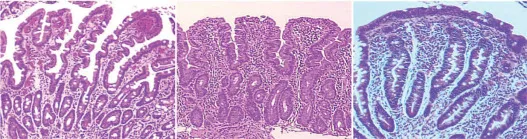

Celiac disease results in damage to the inner surface of the small intestine (Figure 1.2), greatly reducing its ability to absorb nutrients. The small intestine is the point of absorption for almost all nutrients (carbohydrates, amino acids, vitamins, and minerals) and can be considered the most important part of the gastrointestinal tract. Over time, malnourishment occurs when it is damaged. The only known treatment of celiac disease is the complete avoidance of wheat, rye, and barley (5). Even ingestion of 20ā50 mg of gluten per day can prevent a full recovery in a celiac patient with damaged intestines (6).